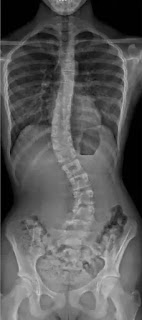

The spine or backbone is not just bones. It is a complicated structure composed of bones, joints, ligaments and muscles. The spinal bones are hollow; they enclose the spinal cord, nerves that pass from the brain to all parts of the body. The human spine is divided into sections named after the portion of the body they pass through: cervical, thoracic, lumbar, sacrum, and coccygeal.